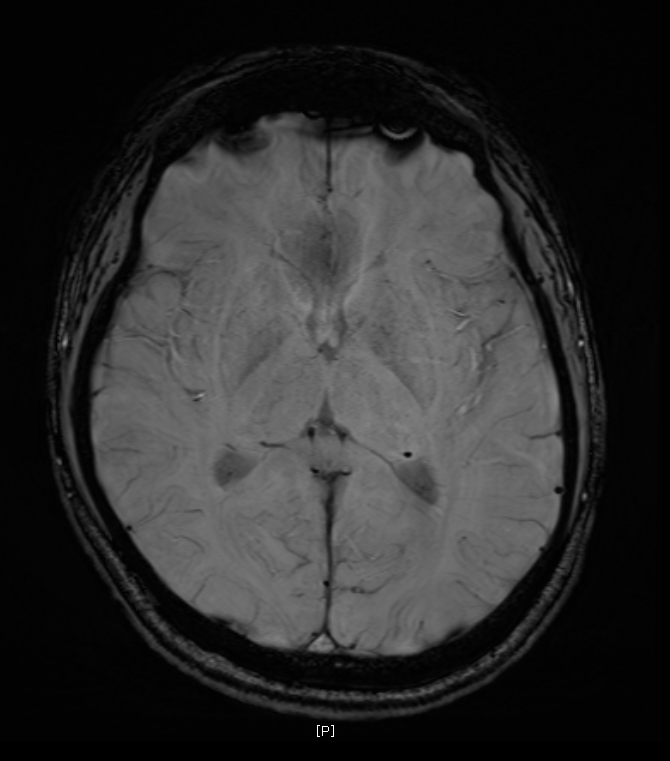

지난 금요일에 MRI를 촬영했는데요

혈관같기도 하고 하얀색 붕붕 뜨는 게 있어보이는데 (혈관같음)

한번 봐주실수 있나요? 그리고 전체적으로 괜찮은지도 봐주시면 감사하겠습니다.

특별하게 눈에 띄는 병변은 있어보이지 않습니다

말씀하신 것은 혈관의 가능성이 높겠습니다